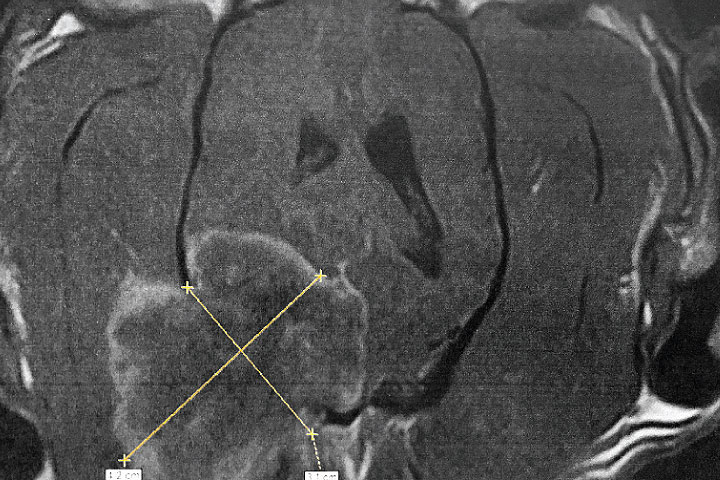

Choroid plexus tumours and Ependimomas

These intra-ventricular tumours cause hydrocephalus and diffuse bilateral symmetric forebrain signs.

They can be differentiated into Choroid Plexus Papilloma or Carcinoma with different growth rates and prognoses. Cerebrospinal fluid protein levels can help to differentiate between the two.

Currently, surgery is not attempted on these types of tumours, however intraventricular peritoneal shunting (VPS) can resolve signs of hydrocephalus temporarily. They usually carry a poor prognosis.